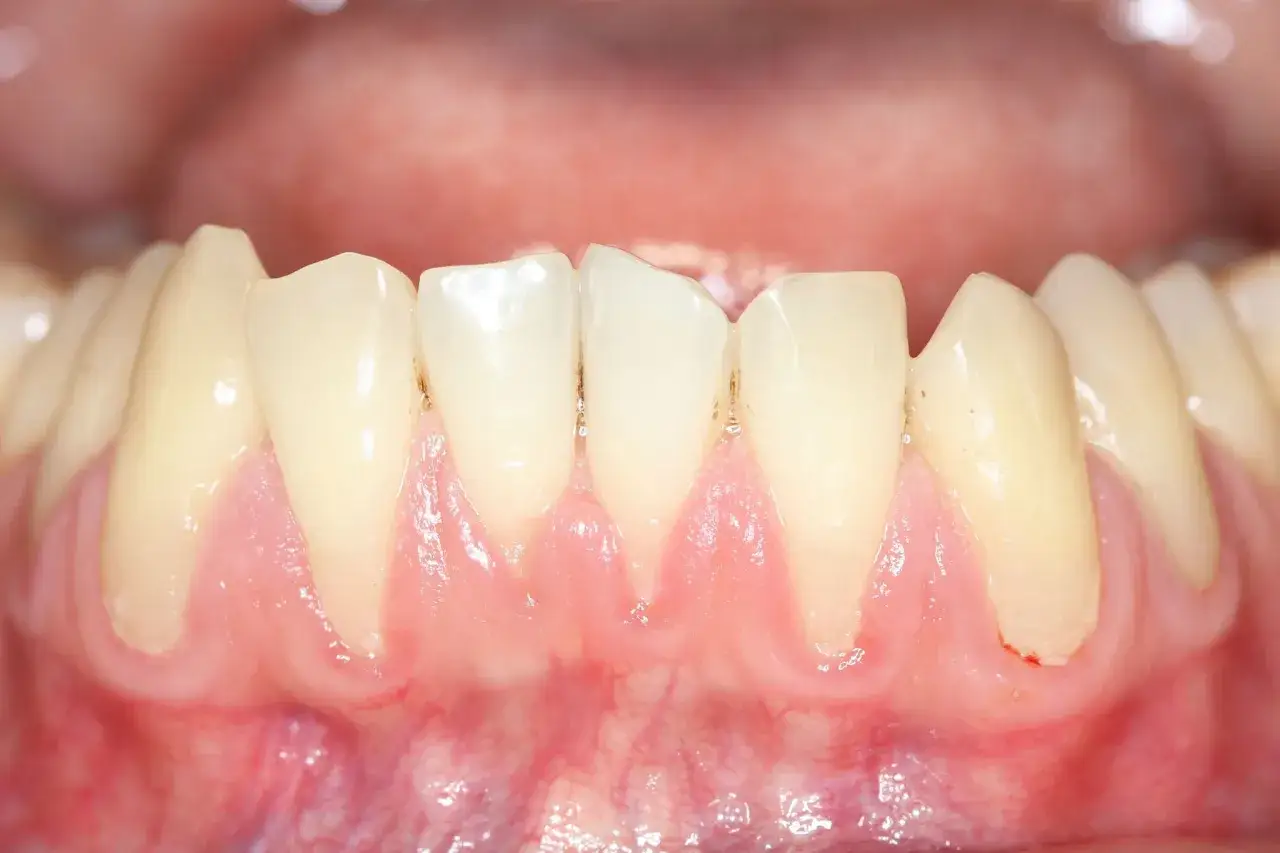

Kolor torbieli może być zróżnicowany. Często bywa ona półprzezroczysta, co pozwala dostrzec płyn w jej wnętrzu. Może przybierać również barwę białawo-żółtawą, zwłaszcza jeśli zawiera treść ropną. Wokół torbieli często obserwuje się zaczerwienienie, świadczące o stanie zapalnym. Co do konsystencji, torbiel może być miękka i elastyczna w dotyku, przypominająca balonik z wodą, ale bywa też twardsza, jeśli rozwija się w gęstszych tkankach lub jest otoczona grubszą torebką. Dotykając ją, można czasami wyczuć charakterystyczne uczucie "chrupania" kości, co jest sygnałem zaawansowanej resorpcji.

Opuchlizna dziąsła i widoczna asymetria twarzy: objawy zaawansowanej zmiany

W bardziej zaawansowanych stadiach torbiel staje się na tyle duża, że jej obecność jest widoczna gołym okiem. Obserwujemy wtedy wyraźną opuchliznę i uwypuklenie dziąsła lub kości. W skrajnych przypadkach, gdy torbiel osiąga znaczne rozmiary, może prowadzić do widocznej asymetrii twarzy. To już poważny sygnał, którego absolutnie nie wolno ignorować, ponieważ świadczy o znacznym postępie choroby.